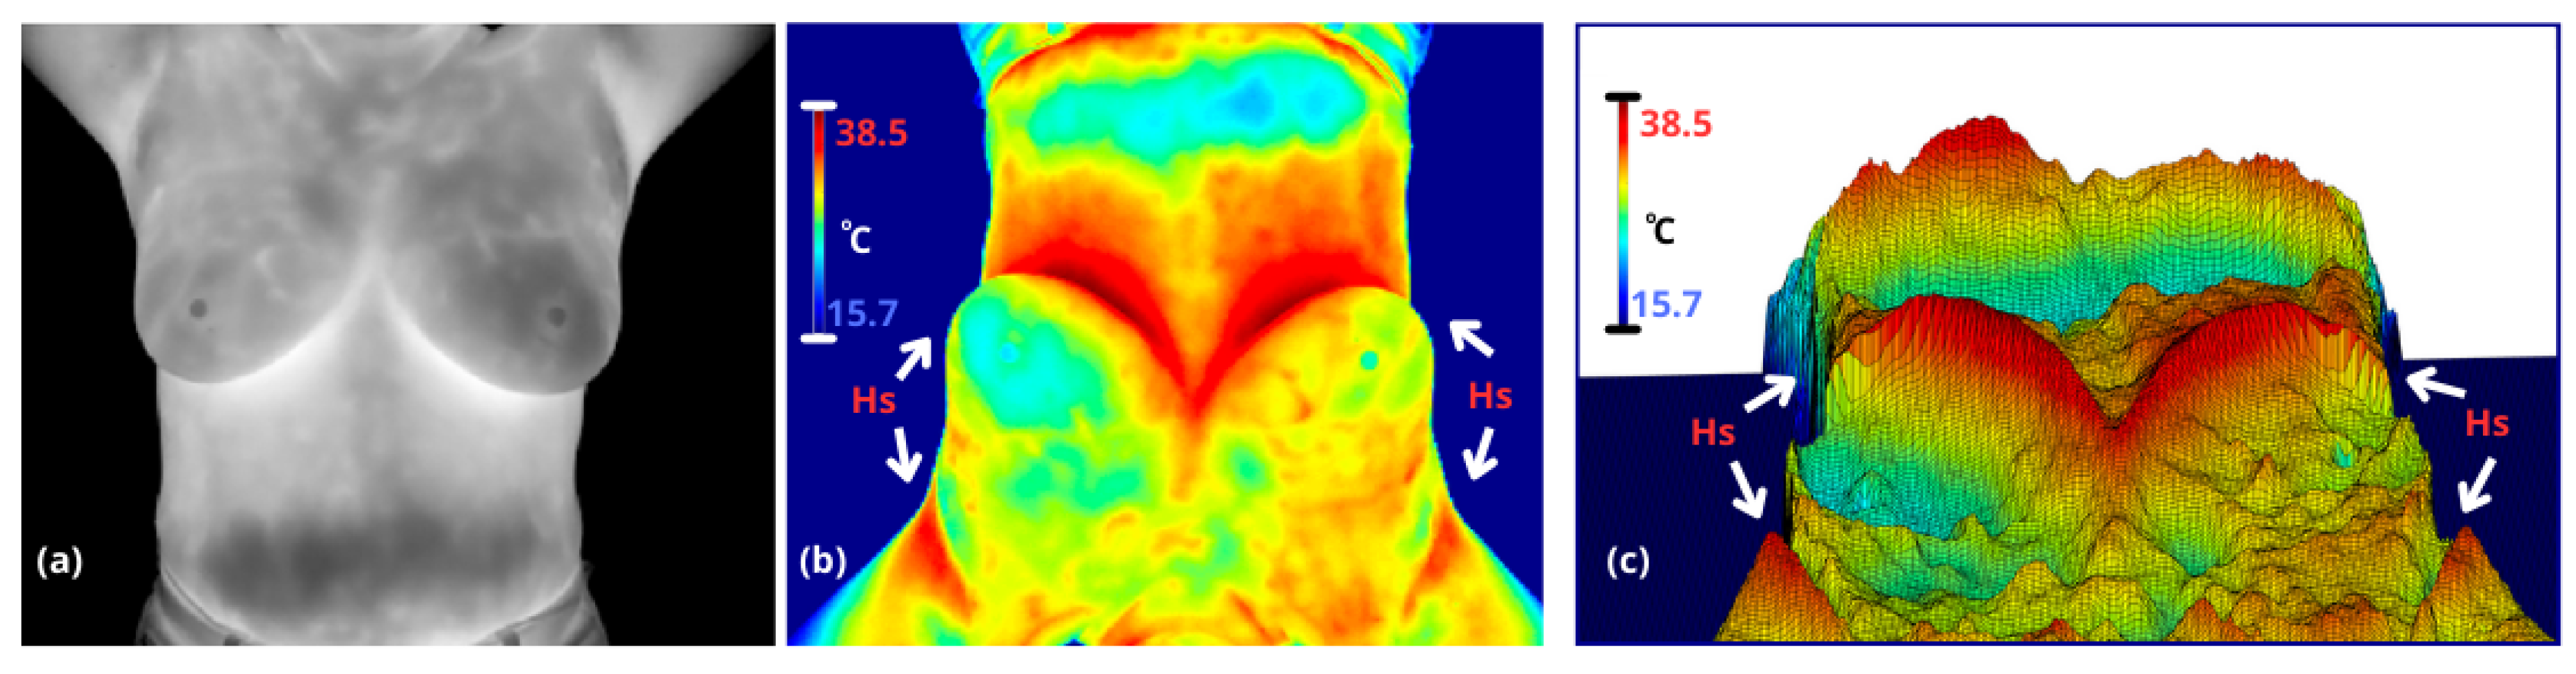

2.1. Anatomic Breast Structure

In a previous work, we proposed a method based exclusively on traditional computer vision to segment breasts in thermal images [20]. This approach enables the evaluation of intra- and inter-breast temperatures, where variations in heterogeneity are often related to pathological angiogenesis (e.g., tumors) or other abnormal thermal asymmetries (e.g., mastitis). In thermal maps, temperature changes induce a contrast between anatomical regions, which are analized based on three classic thermal patterns to define breast boundaries: armpits are characterized by a high concentration of sweat glands, limited ventilation, and proximity to major blood vessels like the axillary artery; body is defined by constant metabolic activity and heat distribution through blood circulation, contributing to thermal regulation; and inframamary region which exhibits a V-shaped thermal contrast—referred to here as the ’inverse V region’—is characterized by skin-to-skin contact, lack of ventilation, sweat glands, and thermal insulation provided by adipose tissue, see Figure 1.

The thermal patterns of the body edges and armpits exhibit high, reproducible contrast under controlled conditions, such as the lower background temperature and the exposure of warm armpits when the arms are raised. While the inframammary region displays significant variability due to its V-shaped thermal contrast, which changes based on breast size, these patterns remain detectable. In contrast, the supramammary border is either virtually nonexistent or highly ambiguous, making it significantly more challenging to define.

Figure 1. (a) A coronal thermography image spanning from the neck to the lower abdomen, where the right breast (appearing on the left in the image) shows heterogeneous regions with higher temperatures compared to the left breast. (b) Thermography (a) with a jet colormap applied, enhancing thermal transition zones through color variations (notably red areas, denoted as hot points (here denoted as Hs). Additionally, the image is rotated 180 degrees (upside down, though still showing the neck) to better highlight the transitions observed in (c). (c) A 3D rendering of the thermography image where temperature intensities are visualized as a topographic relief. Hot points (Hs) appear as hills, providing a clear visual contrast, while cooler regions, such as the lower abdomen, resemble valleys.